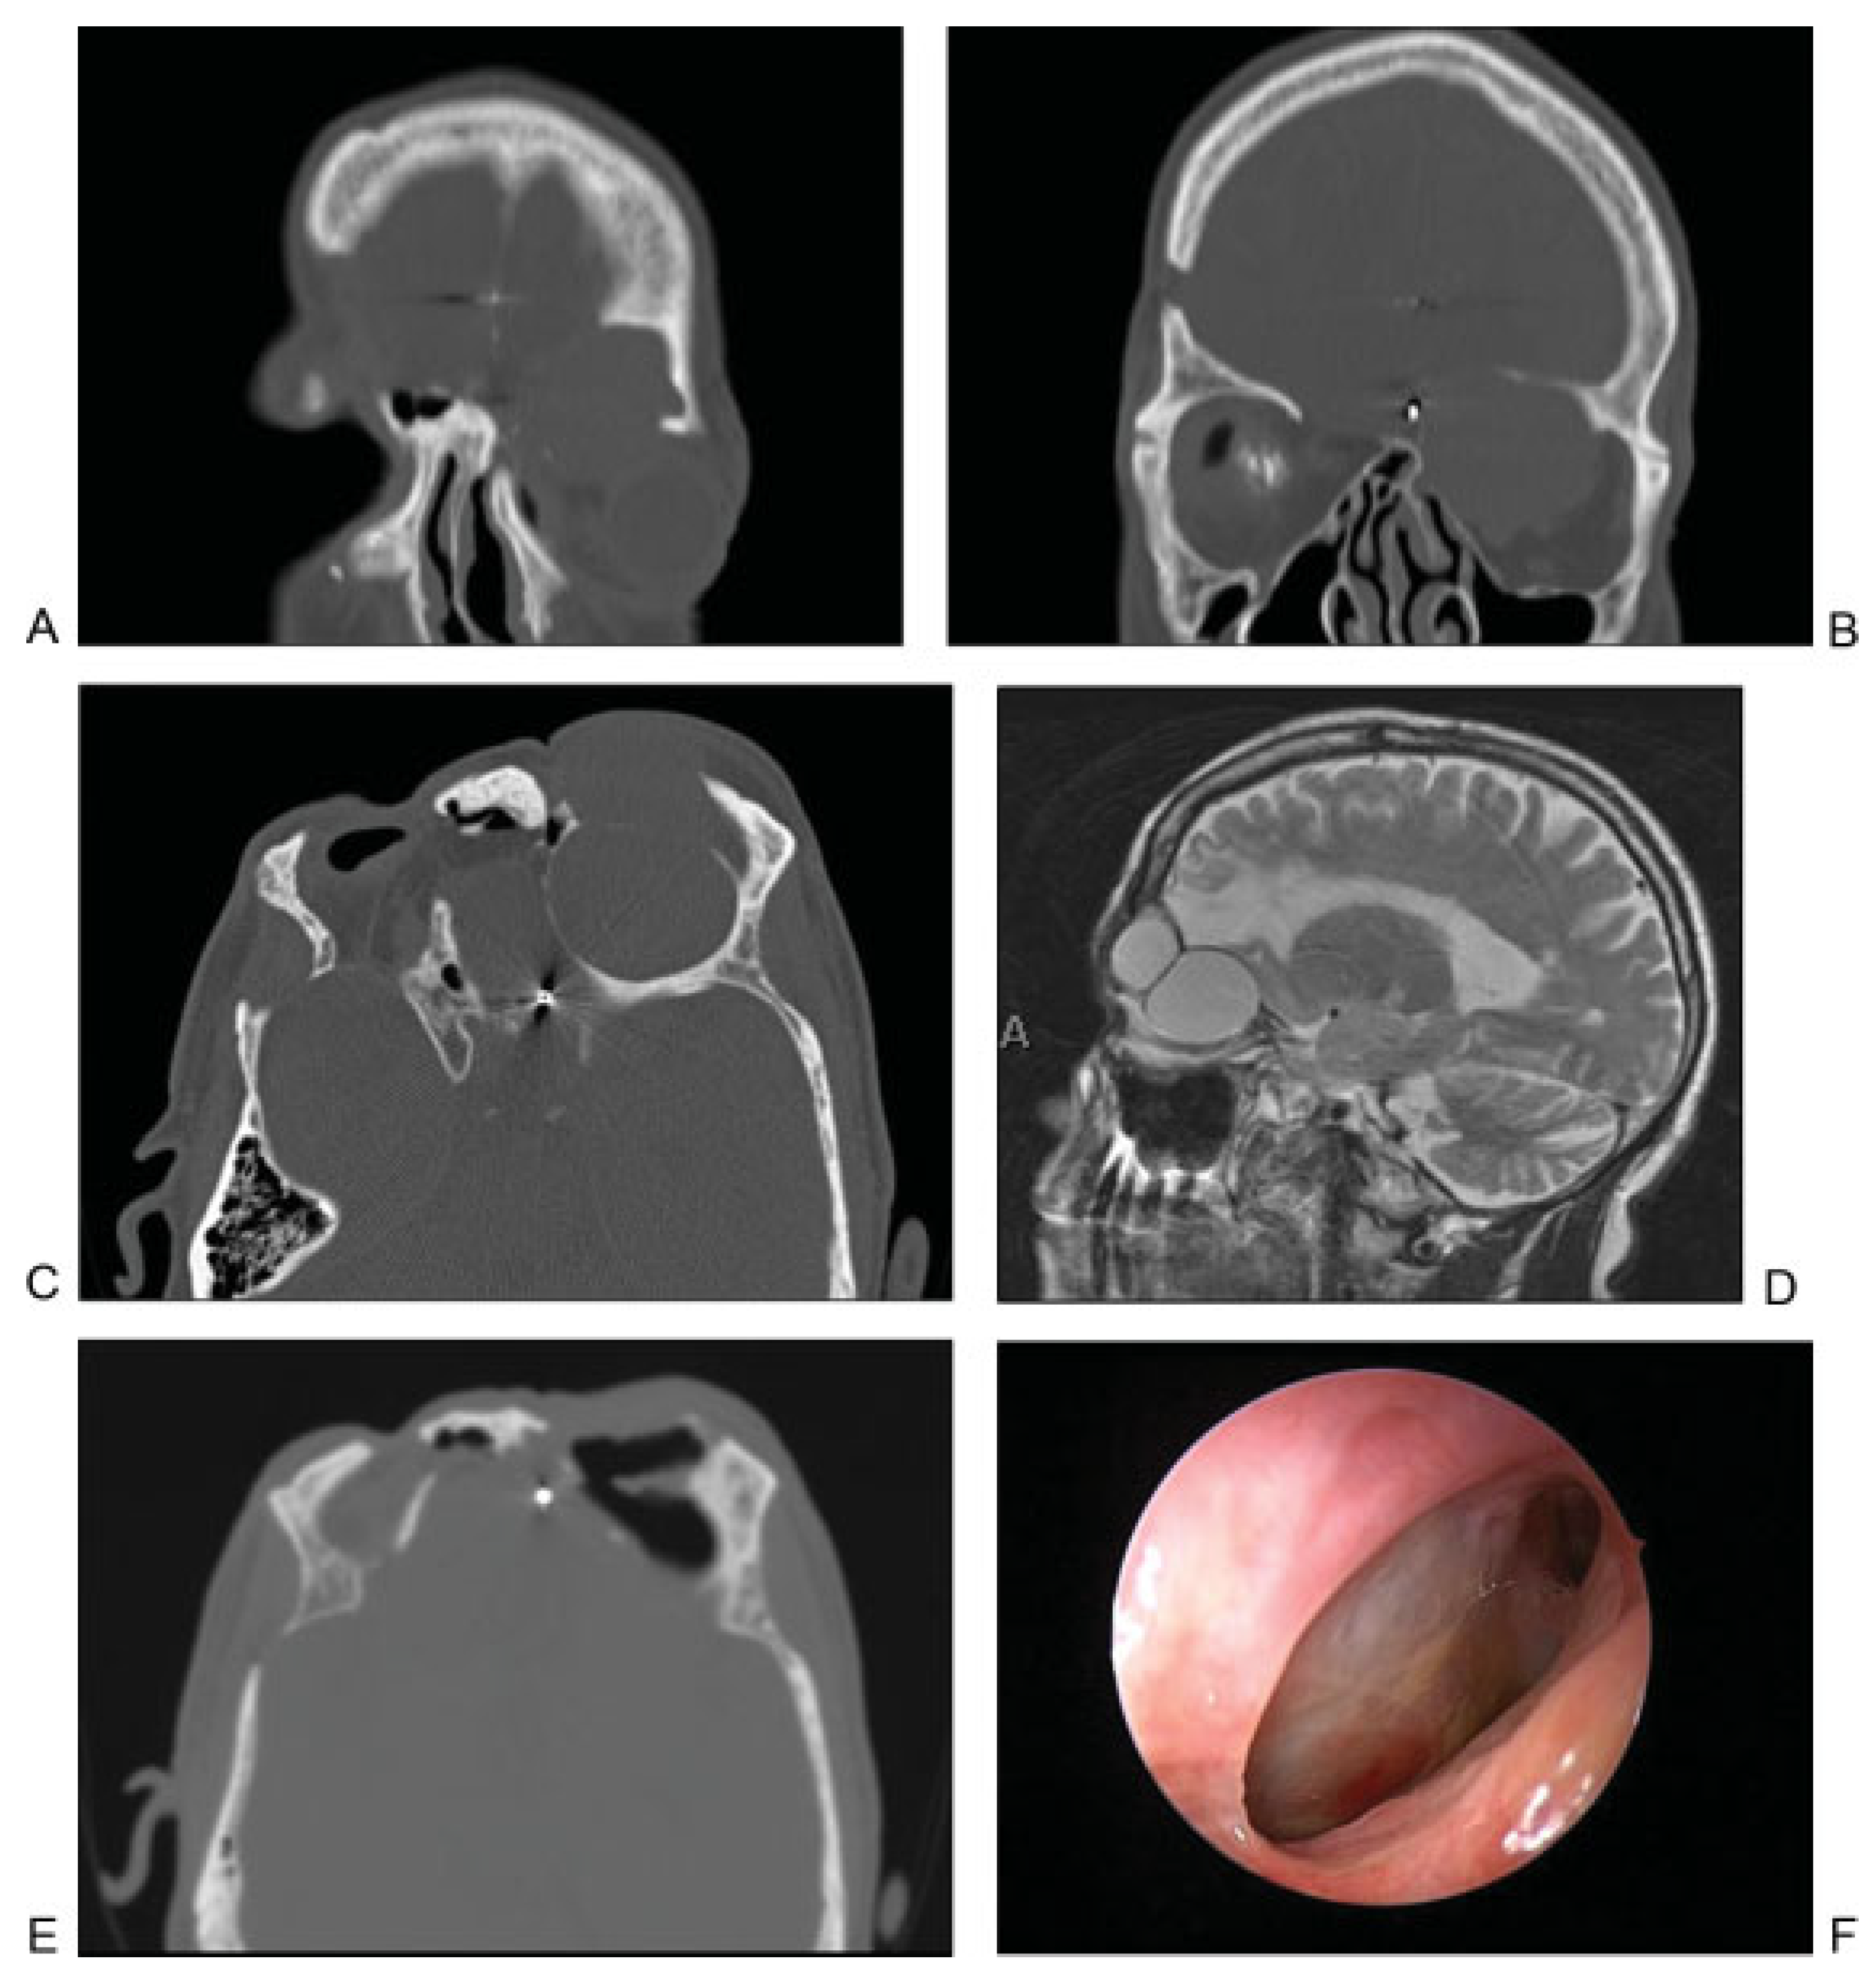

Figure 5.

(A) Coronal computed tomographic (CT) image showing mucocele that developed in a delayed fashion after extensive frontal sinus trauma and previous cranialization. Image shows mucocele with orbital and intracranial involvement. (B) Coronal CT image showing orbital mucocele. (C) Axial CT image demonstrating two separate mucoceles involving the left frontal and orbital regions. (D) Sagittal MRI demonstrating two distinct mucoceles. (E) Postoperative axial CT image demonstrating aeration of both mucocele cavities after endoscopic marsupialization. (F) Postoperative endoscopic view of the outflow tract of the two mucoceles after complete healing.

Figure 7.

(A) Axial computed tomographic showing fractures of the posterior aspect of the right frontal sinus and the intersinus septum. A frontal sinus trephination approach was used to manage this defect. (B) Intraoperative picture showing a drill being used to perform the trephination and expose the frontal sinus lumen. (C) Endoscopic view of the frontal sinus lumen through the trephination shows a small area of brain herniation (black arrow) into the frontal sinus through the posterior table defect. Endoscopic visualization also shows a patent frontal sinus outflow tract (white arrow). (D) After encephalocele cauterization, repair was performed using a bone graft and mucosal graft. Image shows mucosal graft in place (black arrow) and that the frontal sinus outflow tract remains patent (white arrow).

The patient in Figure 7A did not have an active CSF leak at the time of initial injury. Imaging showed a fracture along the posterior frontal sinus wall. In the absence of a CSF leak, no acute exploration or repair was performed. The patient presented 2 years later with an episode of meningitis. Imaging revealed an encephalocele at the site of the previous posterior wall injury. The defect was repaired by way of a frontal sinus trephination approach, as shown in Figure 7B–D. In this case, the defect was repaired using bone and mucosal grafts while maintaining a patent frontal sinus outflow tract.